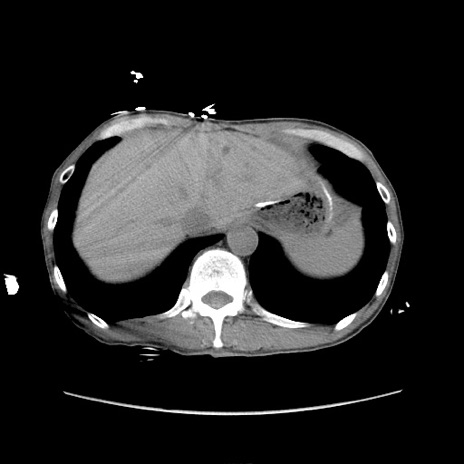

冠状断像

【症例】 60歳代男性

【主訴】 下腹部痛

【現病歴】 本日夜中より下腹部痛の症状認め、受診。

【既往歴】 膀胱癌(膀胱全摘+尿管皮膚瘻術) 、胃癌術後

【身体所見】 BT 35.3℃、PR 58/min、BP 136/98mHg、腹部平坦、軟、腸蠕動音±、ストマ留置あり、左上腹部~正中部に圧痛あり、反跳痛なし。

【データ】WBC 5100、CRP0.01